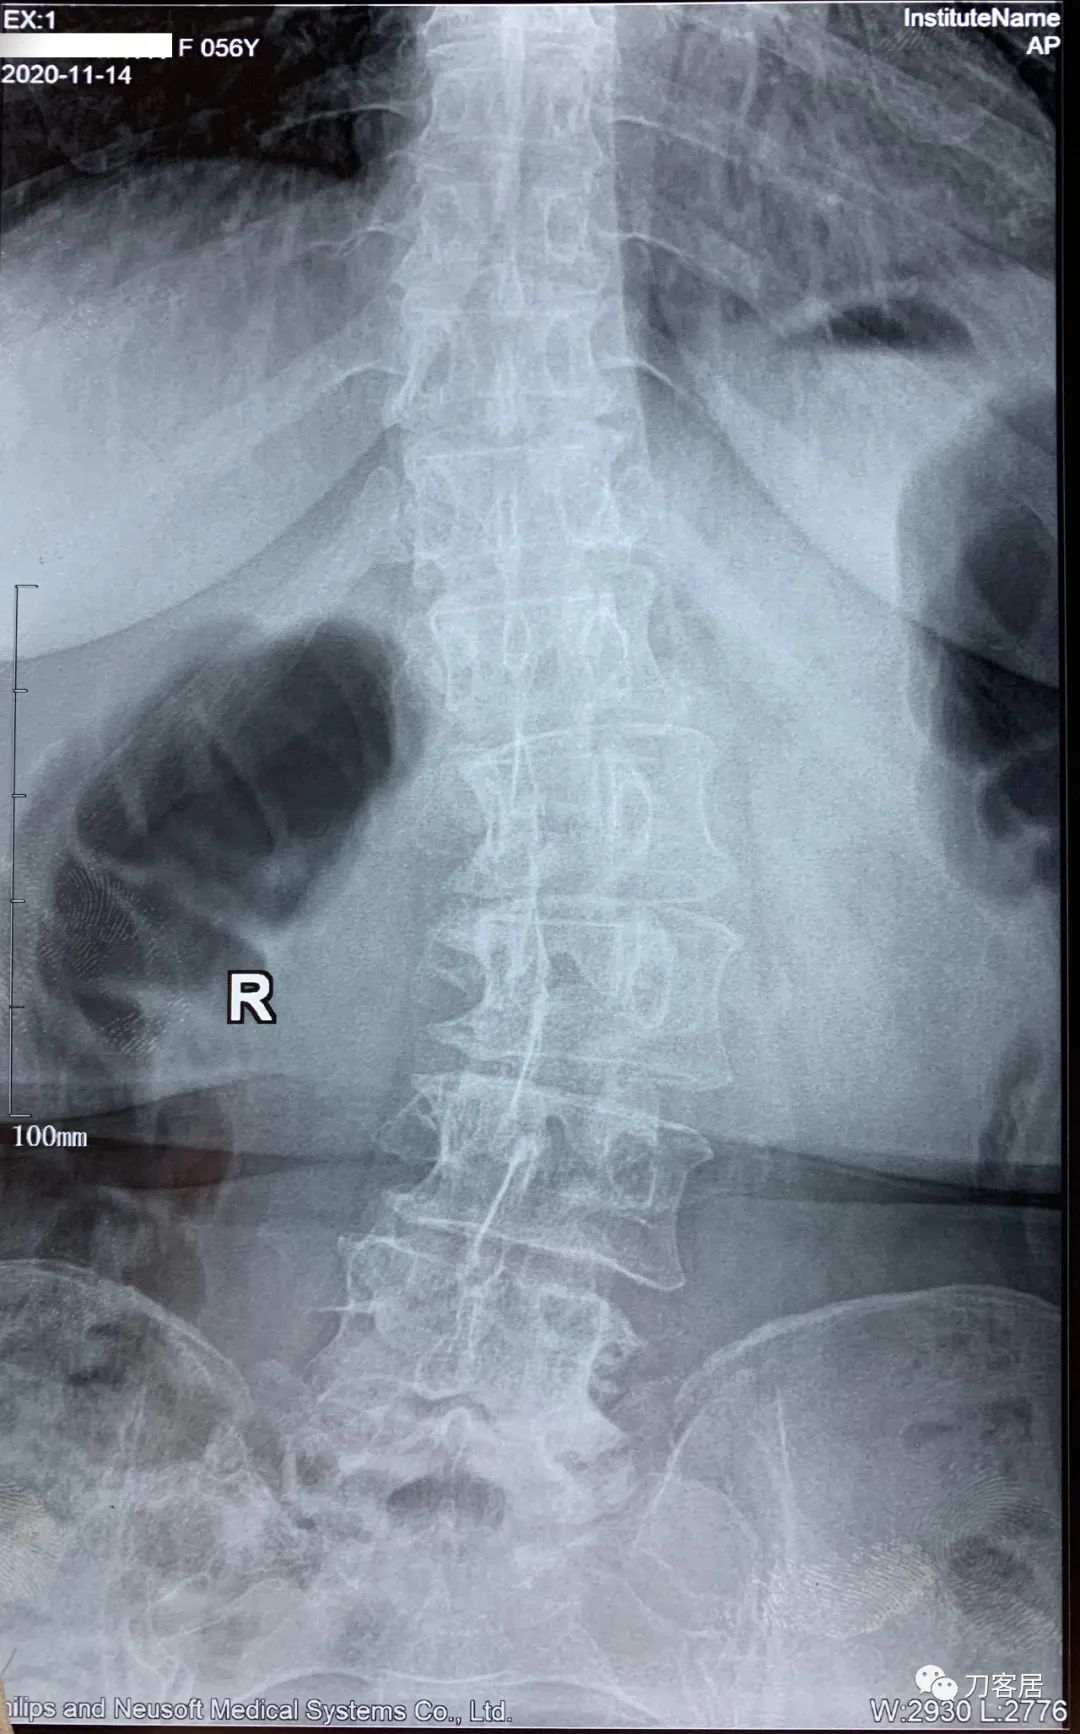

患者自2020年8月4日始头晕,2020年8月25日双手麻,双胳膊麻,于兰大二院定西分院检查颈椎MRI及腰椎X线片, 提示1. 颈椎生理曲度变直,2. 颈椎骨质增生,3. 颈椎间盘变性,颈4-7椎间盘轻度膨隆,4. 腰椎侧弯畸形。

2021年5月17日,西京医院骨科门诊找我就诊,自带影像学检查资料提示腰椎侧弯,腰3-4,腰4-5椎间盘突出,黄韧带肥厚,椎管狭窄。

建议其查双光子骨密度,骨盆正位片以及腰椎间盘平扫。腰椎正侧位X线片以及动力位片,站立位脊柱全长正侧位X线片,以了解其是否有骨质疏松,并了解脊柱侧弯情况,腰椎局部X线表现情况和腰椎间盘突出和椎管狭窄情况。

从这个患者的影像资料分析,颈椎间盘突出问题不大,没有明确的上位神经元损伤表现,所以,不考虑颈椎和胸椎问题。腰椎侧弯畸形,但不严重。因为存在腰椎侧弯,使得腰椎MRI在扫描切面的时候,显示的椎间盘突出或椎管狭窄会有一定的误差,所以,又加做了经椎间盘的CT平扫,影像表现并不严重,综上,腰椎间盘突出,腰椎管狭窄,腰椎侧弯,不考虑手术治疗。同时,患者的主要痛苦是心理疾病,而不是器质性疾病,所以,以心身疾病治疗为主。虽然患者骨密度检查结果提示正常,但X线片显示骨质疏松,且其症状也与骨质疏松的症状有符合之处,比如静息痛,不能入睡,动作及姿势变换时痛加重等,所以,给予实验性抗骨质疏松治疗,以观疗效。